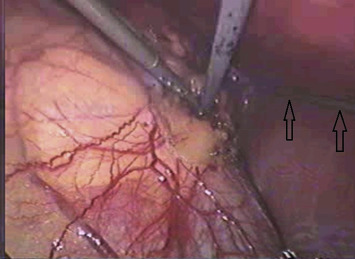

Intraoperative view of pure needlescopic-instrument clipless right adrenalectomy ...

Figure 1.

Intraoperative view of pure needlescopic-instrument clipless right adrenalectomy where the 2-mm liver retractor (arrows) lifted the liver up smoothly without any spacer via running parallel to the undersurface of the liver.

The authors did not specify where they inserted the needlescopic grasper, but roughly mentioned that it is from a separate stabbing wound apart from the laparoendoscopic single site (LESS) platform. In their Figure 1,1 the axis of the needlescopic grasper was perpendicular to the liver, which made the spacer mandatory in preventing the grasper from penetrating the liver. However, both Gill et al2 and our group3 ;  4 have published the application of needlescopic instruments during multiport needlescopic adrenalectomy, and in all cases the needlescopic liver retractor was inserted via a subxyphoid stabbing wound, which made the axis of the liver retractor parallel to the undersurface of the liver, and it lifted the liver away from the right adrenal gland (tumor) easily without the necessity of a special spacer (Figure 1). For the left needlescopic adrenalectomy, we rarely needed any assisting instrument to lift the spleen away, because adequate release of the spleen from its lateral peritoneal attachment and spenorenal ligament makes the spleen fall away from the left adrenal gland via gravity.3 ;  4